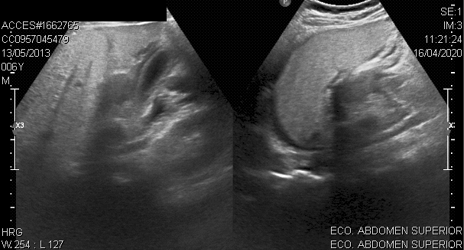

Mientras que dentro del estudio de TAC de abdomen realizado a 13 pacientes el principal hallazgo fue la presencia de líquido perivesicular en 4 (30,76%) de ellos (figura 1 y 2).

En la ecografía de abdomen realizada a 24 pacientes se encontró el mismo hallazgo en 5 casos (figura 3).

Figura 3. Estudio ecográfico en el que se visualiza vesícula biliar poco distendida con líquido libre perivesicular

Fuente: Departamento de Imágenes Hospital Dr. Roberto Gilbert Elizalde